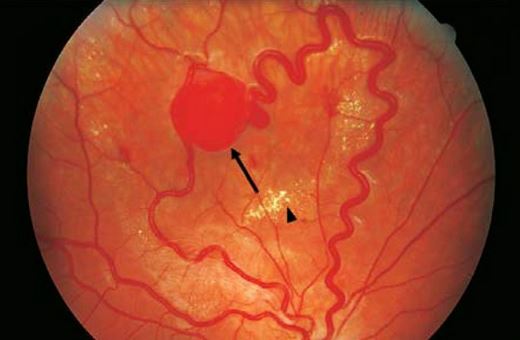

image

Ангиоматоз сетчатки глаза

Офтальмоскопия с измерением внутриглазного давления

1. Обнаружение ангиоматозно-измененных сосудов на глазном дне.

2. Повышенное внутриглазное давление, свидетельствующее о формировании глаукомы.